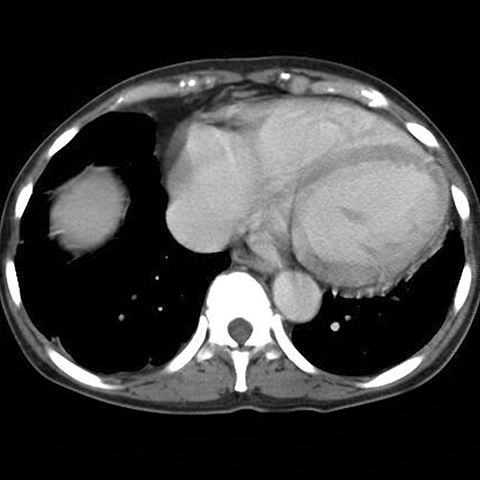

35-year-old male with sickle cell anemia and abdominal pain .